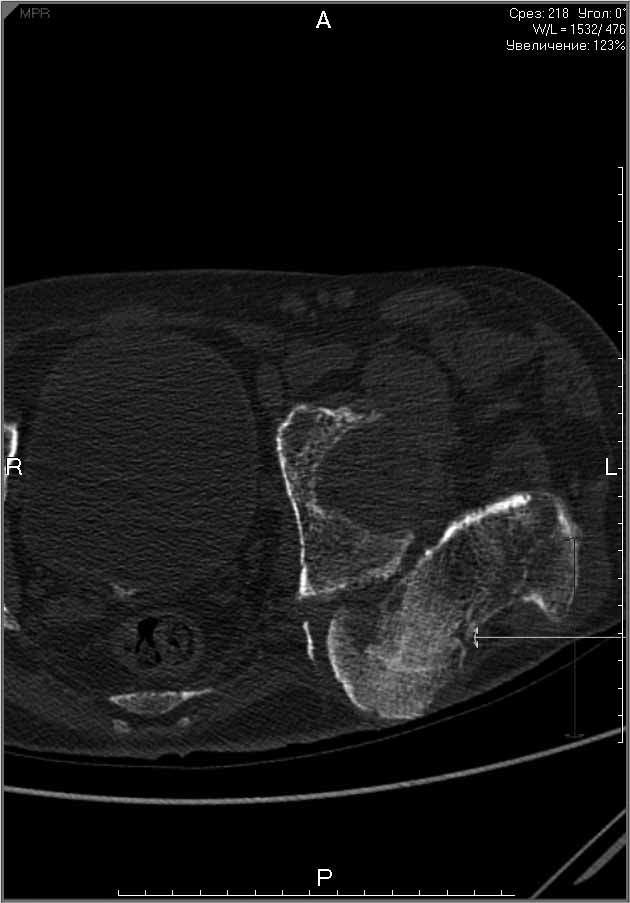

Пациенту 22 года. Травма в июле 2010г, лечился в районной больнице. К нам попал в апреле 2011г.Тяжелая сочетанная травма (29.07.2010): тупая травма живота с повреждением внутренних органов. Закрытая травма грудной клетки с переломом ребер. Пневмоторакс справа. Тяжёлая позвоночно-спинномозговая травма. Закрытый осложнённый переломо-вывих С5 позвонка. Верхний парапарез, нижняя параплегия, нарушение функции тазовых органов по типу недержания. Цекостома. Пролежень левой ягодичной области. Неправильно консолидированные переломы верхних третей обеих бедер. Застарелый вывих левого бедра.Осложнение: Поддиафрагамльный абсесс слева, забрюшинного пространства. Свищ желудка и ободочной кишки. Синегнойный сепсис. Двухстороняя пневмония. Но это уже анамнез.Пациент был неоднократно оперирован на органах брюшной полости и осложнениями с ними связанными.

В ягодичной области слева глубокий пролежень размером 2х2см, дном является вывихнутая головка бедра. Неврологически в нижних конечностях динамика положительная, появились движения в правой стопе, чувствительность в стопах.По переломам бедер: подвижности в местах переломов нет, снимки высылаю.

Мне кажется, что нудно начать с резекции головки левого бедра (как минимум - вы устраните очаг хр. инфекции) далее заниматься закрытием стом и правой стороной (судя по неврологической динамике).К левой стороне можно вернуться позже, если понадобится.